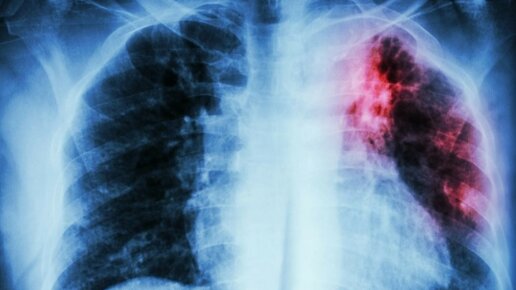

Туберкулез — это инфекционная болезнь, передаваемая воздушно-капельным путем. Вызывают ее микобактерии, или палочки Коха. Они развивают воспаление тканей с образованием гранулём и очагов некроза, вследствие которых развивается общая интоксикация организма. В основном, туберкулез поражает лёгочную систему, но может распространяться и на другие органы: костную ткань, кожные покровы, кишечник. По статистическим данным, туберкулез находится в десятке самых частых причин смертности. Как передается туберкулёз...

Туберкулез является инфекционным заболеванием. Ежегодно туберкулезом заболевает множество людей, при том, что инфекция может долгое время быть не выявлена. Возбудитель туберкулеза (палочка Коха) чаще всего поражает легкие, но также может затронуть суставы, кости, глаза, кожу и другие системы организма. Как передается туберкулез? Чаще всего туберкулез передается воздушно-капельным путем. Капли мокроты зараженного человека высыхая поднимаются в воздух, так можно вдохнуть инфекцию. Также туберкулез может передаваться через употребление в пищу молока или мяса больных животных...

Туберкулез — опасное инфекционное заболевание, вызываемое палочкой Коха (бактерия Mycobacterium tuberculosis). Главная мишень — легкие, но туберкулез способен поражать практически любые органы человека, включая кости и почки. NEWS.ru поговорил с врачом общей практики Видновской больницы Заремой Тен и узнал, как избежать заражения и что делать, если диагноз поставлен. Передача происходит воздушно-капельным путем при кашле, чихании или разговоре больного с активной легочной формой. Ключевая особенность...